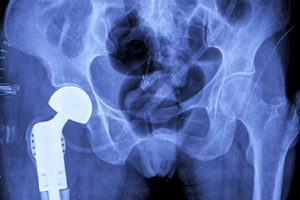

Metal on metal (MoM) hip replacements implanted since 2006 are more prone to failure and patients with them have a greater need for further surgery, finds research looking at revision rates at one hospital trust for the DePuy Pinnacle device.